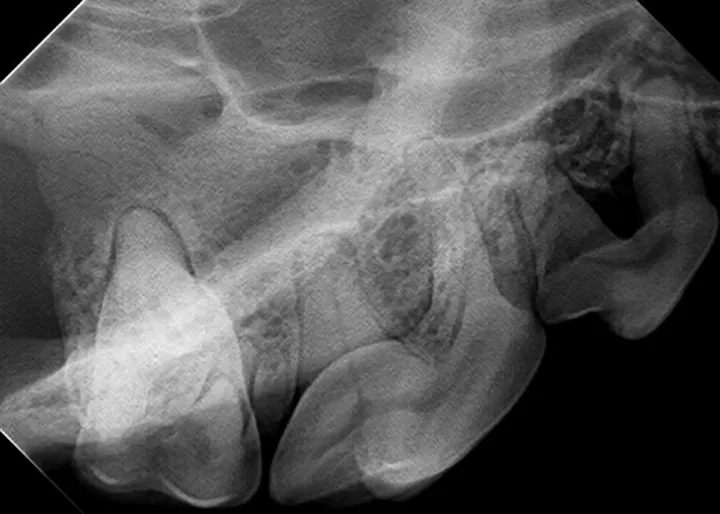

A thorough assessment with full mouth radiographs is an important part of a Comprehensive Oral Health Assessment and Treatment (COHAT). The goal is to find pathology and provide appropriate treatment to prevent oral pain. However, time management concerns and a steep learning curve often deter veterinary professionals from performing dental radiographs on a regular basis.1

The following techniques can ease this process for veterinary technicians and ensure the quality of dental radiographs and patient care.

If a digital intraoral system is used, the goal is to achieve radiographs within 5–10 minutes for a cat or small dog and within 15–20 minutes for a large dog. Hands-on training and cadaver practice will significantly decrease the time needed for acquiring a full mouth series of radiographs.